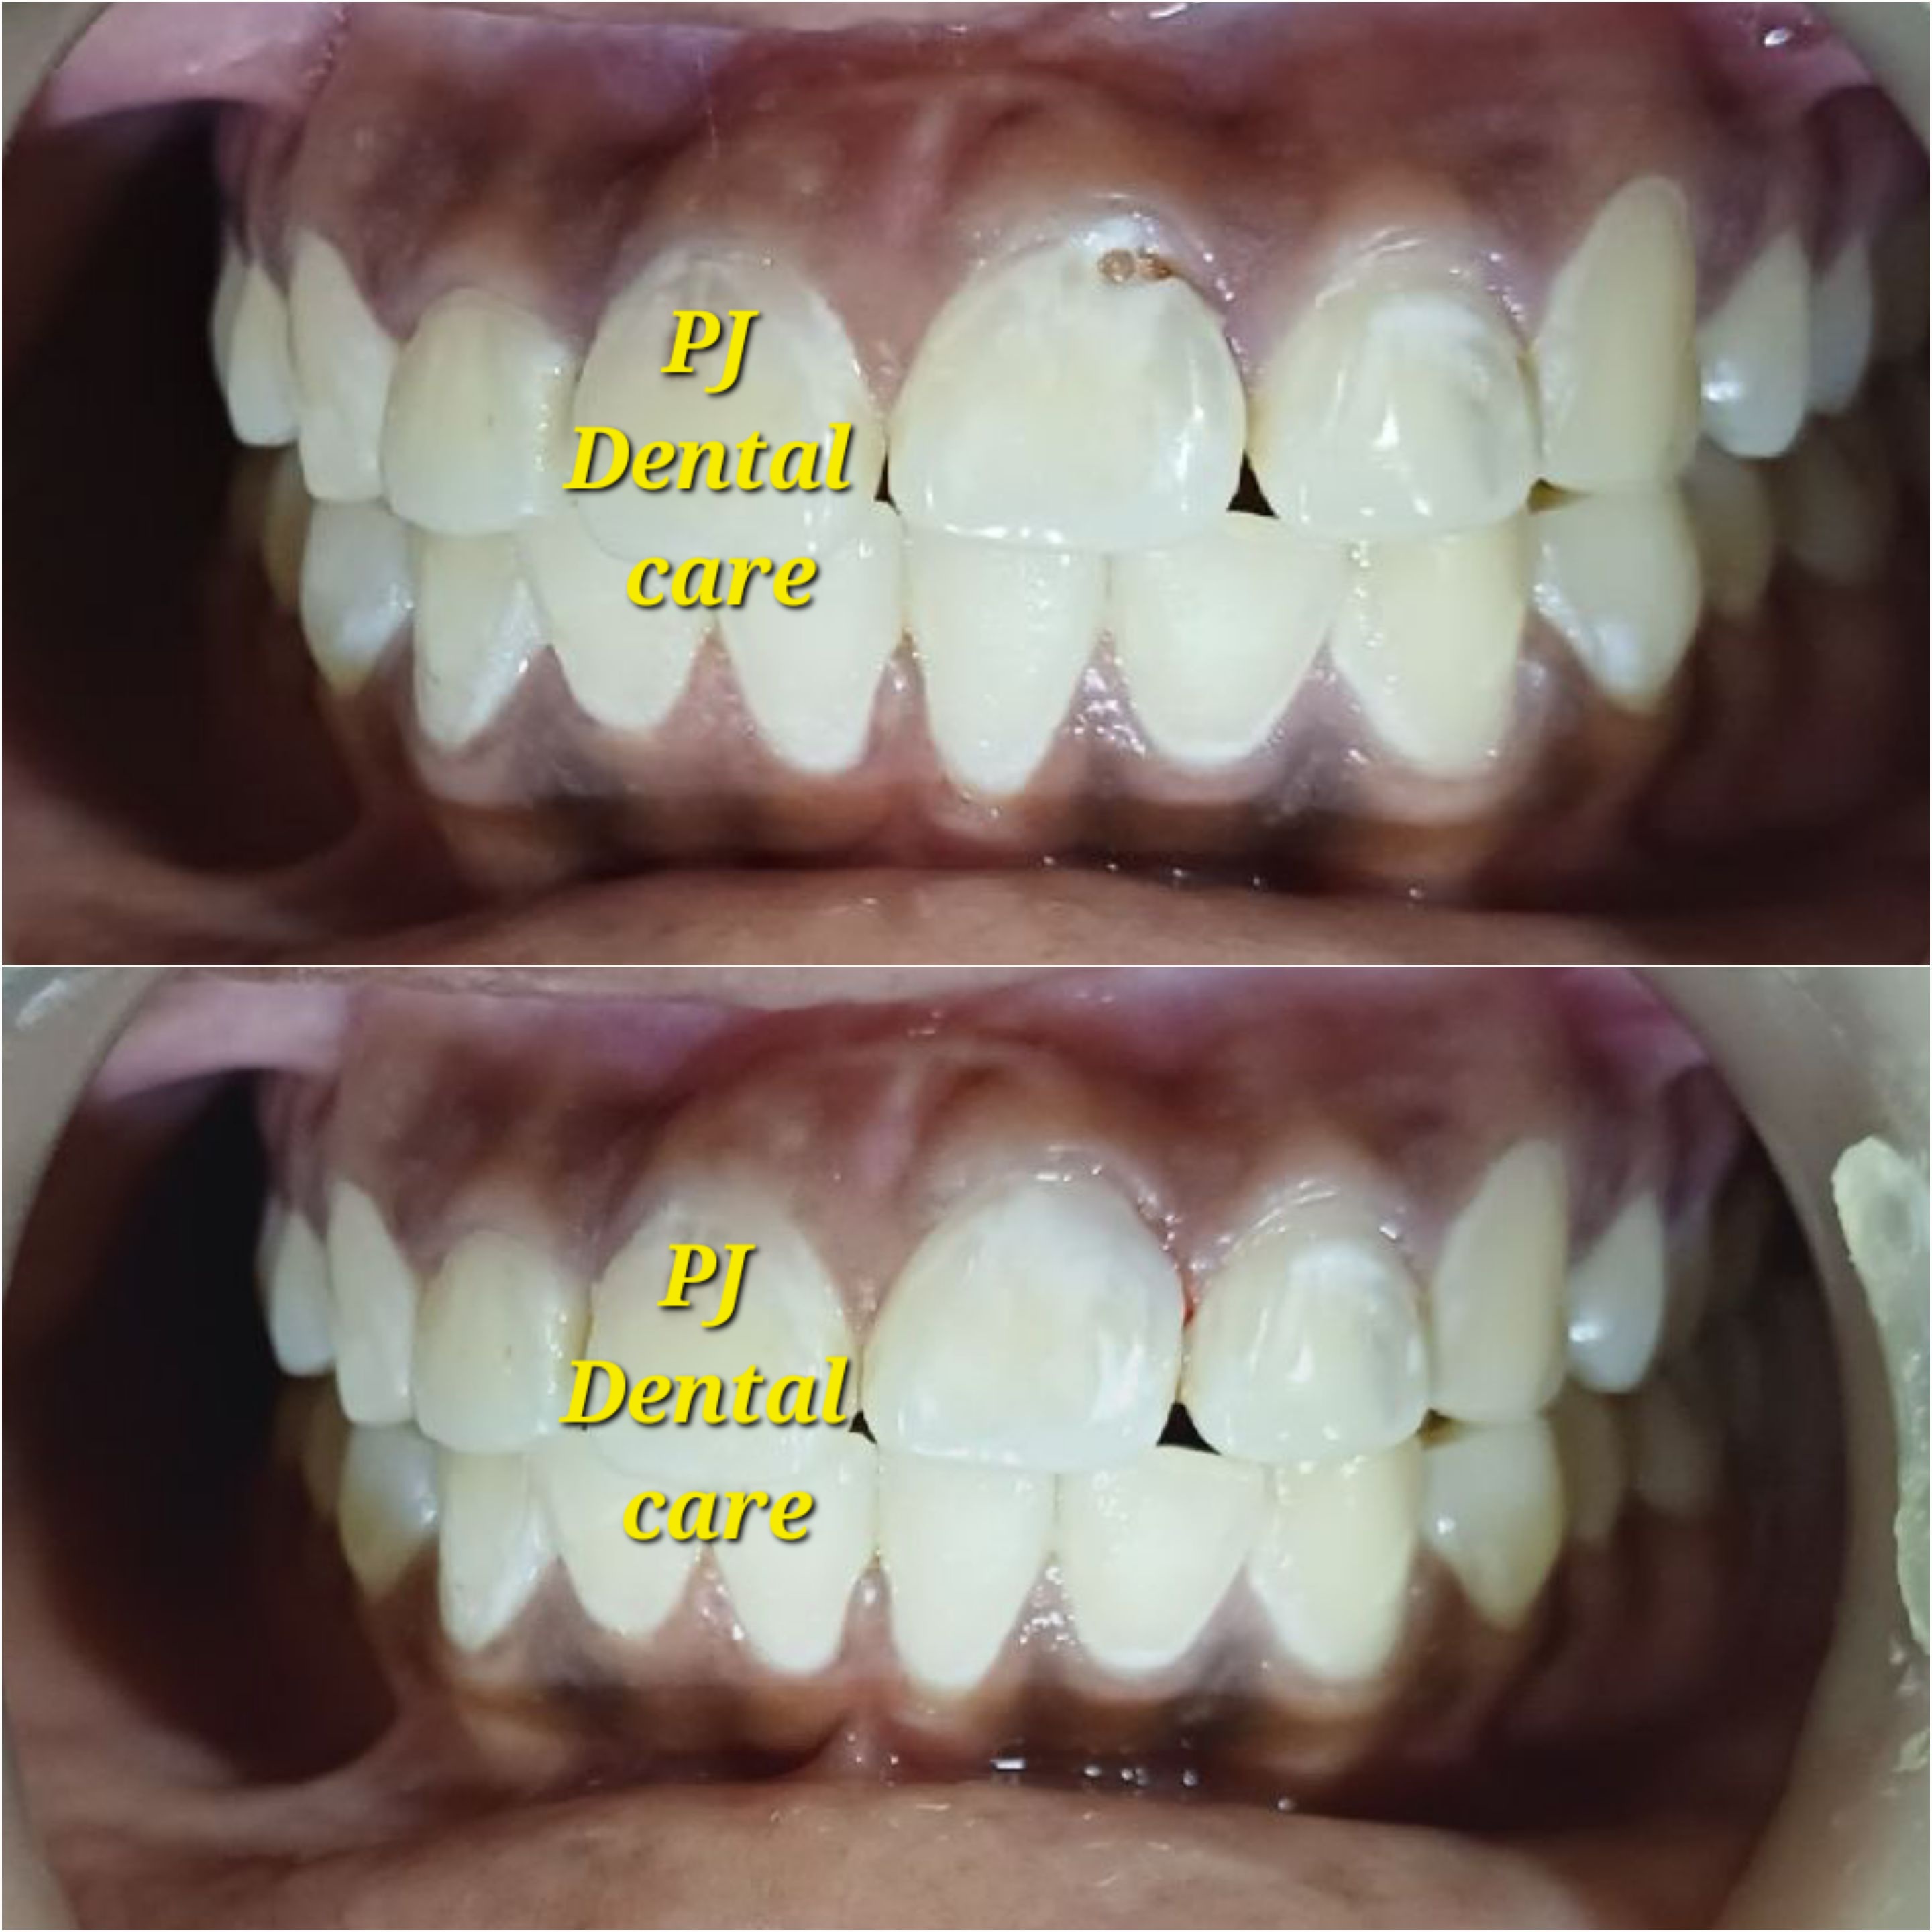

Your leading choice for dental, laser, and permanent makeup services in Tirupati. PJ Dental and Aest... hetics (Ph: 9148118616) offers affordable implants, root canals, laser hair reduction, lip blush, and more since 2012. We ensure the best treatment outcomes at reasonable prices. Read more